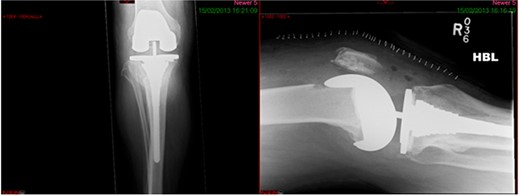

A 68-year-old gentleman who was diagnosed with a Schatzker type VI fracture having fallen 3 m from a ladder (Figs 1 and 2). The injury was closed and neurovascularly intact. The patient was monitored for signs of compartment syndrome. He rapidly developed significant fracture blisters that persisted for over 2 weeks despite regular dressing care. He was deemed too high risk for acute operative intervention because of a high risk of wound complications. Following a multidisciplinary team discussion, he was managed in a cast then a knee brace, mobilising non weight bearing for 12 weeks, at which point the fracture was seen to be healing in a valgus malalignment. The patient was allowed to partially weight bear and received physiotherapy. He was reviewed regularly until fracture had united (Fig. 3). At 8 months post-injury, the patient underwent total knee arthroplasty utilizing a Depuy Synthes (Warsaw, In) PFC Sigma TC3 tibial metaphyseal sleeve and stem, and femoral component without sleeve or stem (Fig. 4). The patient was reviewed post-operatively in clinic at 6 months, the wound had fully healed and the range of motion was 0°–120°. The patient’s pain was significantly reduced, and they were independently mobile. They were kept under annual review and seen at 5 years post-operatively with an Oxford Knee score of 35; the patient used no walking aids and was pain free at rest or during normal walking, with the radiograph demonstrating good osseointegration. The latest follow-up at 8 years revealed no radiographical change in implant (Fig. 5).